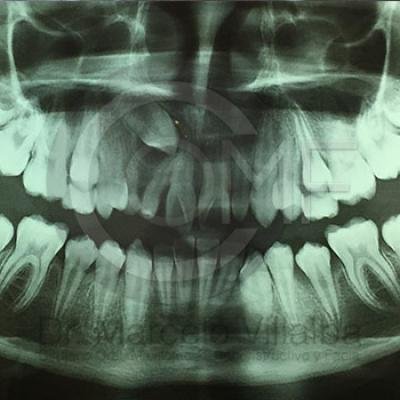

Canino Retenido1